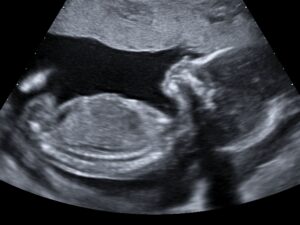

10 Weeks

At approximately 10 weeks we can start to see small arm and leg “buds”. Your baby will start to look like a jelly baby.